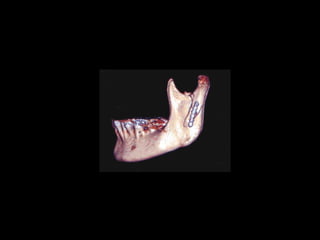

Antilíngula

Obtenido de casos de internet